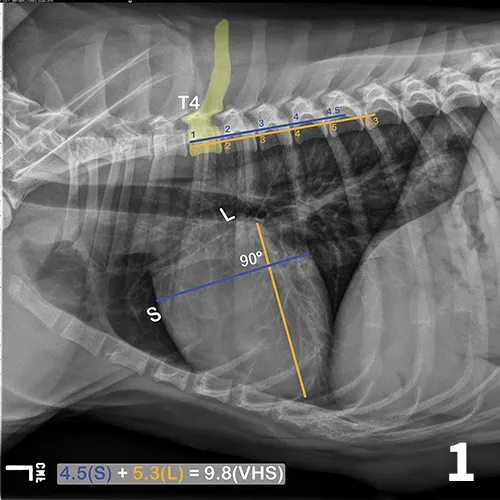

A lateral thoracic radiograph of a normal dog with measurements added to evaluate heart size compared to the thoracic vertebrae.

FIGURE 1

Illustration of VHS calculation in a normal dog. On a lateral radiograph, a line is drawn from the carina to the most ventral aspect of the heart. This line is the “L” or long axis line. A line is drawn perpendicular to the long axis at the widest portion of the heart, extending to the cranial and caudal borders. This is the short axis or “S” line. These lines are transposed using calipers extending along the spine from the cranial aspect of T4. The number of vertebrae traversed (rounded up to the nearest tenth) are added together for the VHS.

The ACVIM consensus statement on degenerative MVD recommends baseline thoracic radiography for dogs with a new murmur, then annually thereafter.6 For practitioners adhering to these guidelines, annual calculation of VHS and rate of change from previous imaging should become standard practice and may help identify those patients at higher risk of developing CHF in the coming year. Figure 2 illustrates annual radiographs taken in a patient with progressive cardiomegaly.

Progressive cardiomegaly noted on annual evaluations in a dog with MVD.